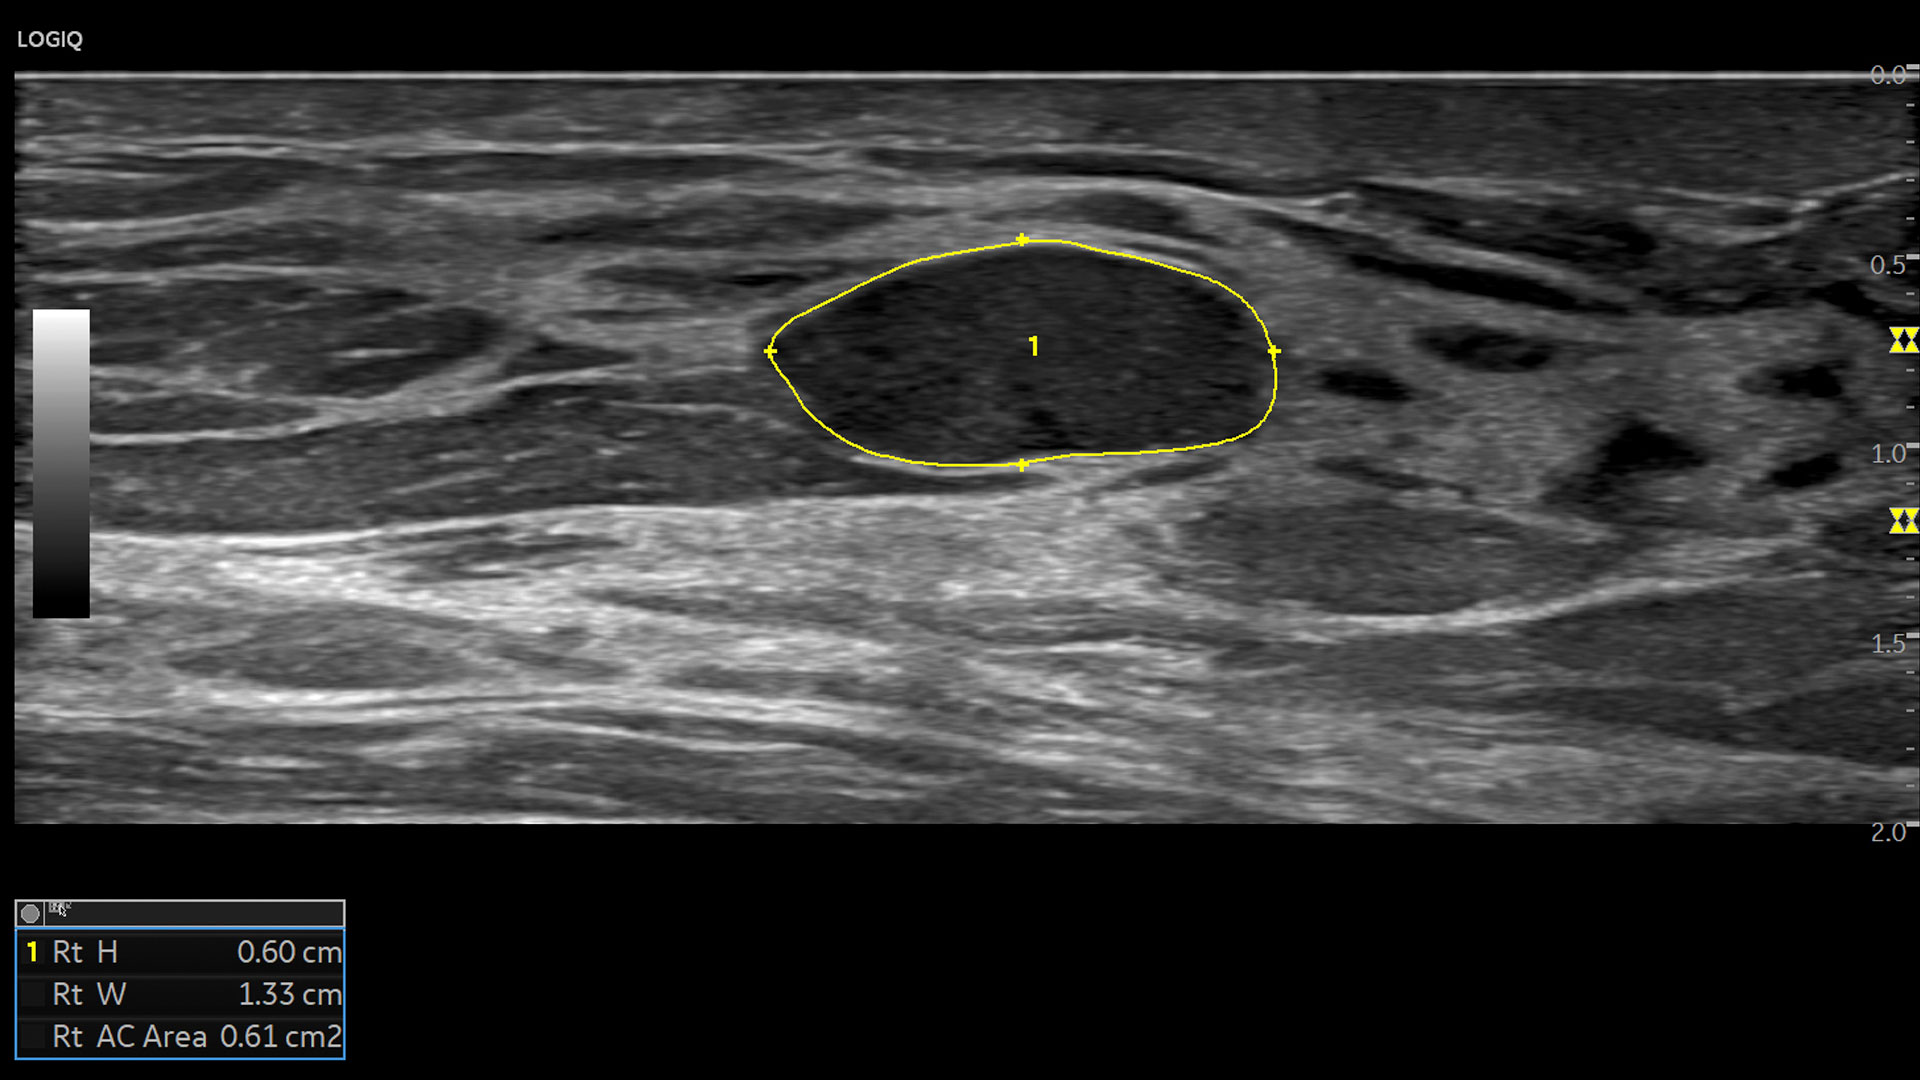

• 2D Shear Wave Elastography

• Ultrasound-Guided Attenuation Parameter (UGAP)

Multi-purpose capabilities, including liver, cardiac, OB/GYN, vascular, breast, thyroid, musculoskeletal, urologic, and pediatric studies.

Superb image quality with XDclear probes: Powerful high fidelity and broad bandwidth produce high resolution images whether scanning superficial or deep targets.

Advanced imaging and visualization tools, including: